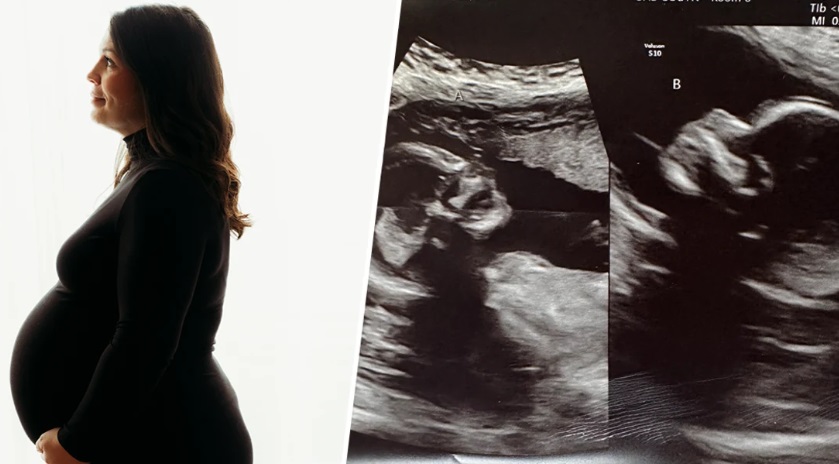

Langka! Kalsey Hatcher, Ibu Hamil Memiliki Rahim Ganda Masing-masing Kandung Anak

Seorang perempuan di Alabama, Amerika Serikat, terlahir memiliki dua rahim. Perempuan tersebut bernama Kelsey Hatcher, kini sedang mengandung lagi. Sebelumnya, pasangan ini memiliki tiga anak berusia 7, 4, dan 2 tahun.

Tetapi, yang membuat kondisi kehamilannya langka adalah karena dua rahimnya masing-masing sedang mengandung bayi perempuan. Kelsey mengetahui dirinya hamil lagi pada musim semi tahun ini. Namun, kehamilannya kali ini mengejutkan dokter kandungannya.

Kalsey dan suaminya Caleb kaget saat pertama kali USG dan mengetahui mengandung dua janin dengan rahim berbeda.